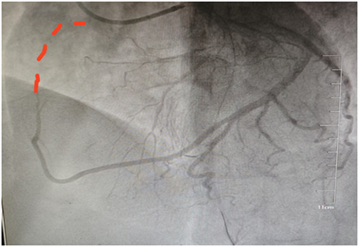

值得一提的是,在造影过程中,医护人员发现患者的右冠状动脉并未闭塞,而是从回旋支发出,这一特殊情况也为手术增加了难度。但凭借精湛的技术和丰富的经验,介入团队成功开通了闭塞的血管,恢复了患者冠脉血流和心肌血液供应。

右冠供血区域由回旋支远段发出的分支提供血液供应。